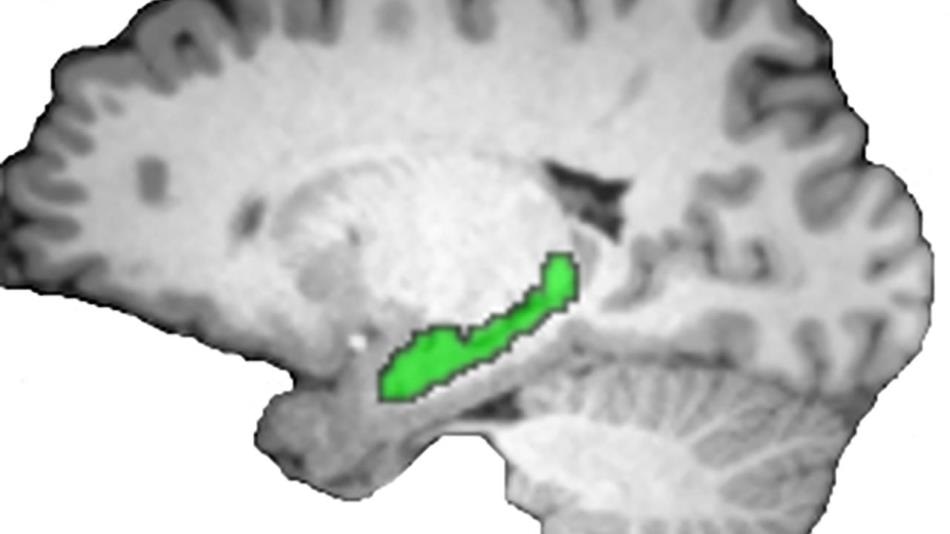

A new brain imaging study shows that the hippocampus (green) is the brain's master storyteller, weaving memories of past events into a coherent narrative. Image: Brendan Cohn-Sheehy, Center for Neuroscience

Cohn-Sheehy and colleagues at Professor Charan Ranganath's Dynamic Memory Laboratory at the Center for Neuroscience used functional MRI to image the hippocampus of volunteers as they learned and recalled a series of short stories.